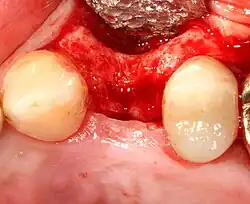

Zavedení implantátu

Většina implantátových systémů má pět základních kroků pro zavádění každého implantátu:[12]:s.214–221

- Odsazení měkkých tkání: Nad hřebenem kosti se provede řez, kterým se silnější přiléhající dáseň rozdělí zhruba na polovinu, takže konečný implantát bude mít kolem sebe silný pás tkáně. Okraje tkáně, z nichž každý se označuje jako lalok, se odsunou, aby se odkryla kost. Zákrok bez laloku je alternativní technika, při níž se pro umístění implantátu místo zvedání laloků odstraní malý úlomek tkáně (o průměru implantátu).

- Vrtání při vysoké rychlosti: Po odsazení měkké tkáně a s použitím chirurgického vodítka nebo stentu se podle potřeby umístí pilotní otvory, a to přesnými vrtáky s vysoce regulovanou rychlostí, aby se zabránilo spálení nebo tlakové nekróze kosti.

- Vrtání při nízké rychlosti: Pilotní otvor se rozšiřuje pomocí postupně se rozšiřujících vrtáků (obvykle tři až sedm po sobě jdoucích vrtacích kroků v závislosti na šířce a délce implantátu). Dbá se na to, aby nedošlo k poškození osteoblastu nebo kostních buněk přehřátím. Chladicí fyziologický roztok nebo vodní sprej udržuje nízkou teplotu.

- Umístění implantátu: Šroub implantátu je zaveden, může být buď samořezný,[29]:s.100–102 nebo se analogicky naklepe do připraveného místa . Poté se zašroubuje na místo momentovým klíčem[32] s přesným krouticím momentem, aby nedošlo k přetížení okolní kosti (přetížená kost může odumřít, což je stav zvaný osteonekróza, který může vést k tomu, že se implantát nedokáže plně integrovat nebo spojit s čelistní kostí).

- Adaptace tkáně: Dásně se přizpůsobí kolem celého implantátu a vytvoří silný pás zdravé tkáně kolem "hojícího se pillíře. Naproti tomu může být implantát pohřben, kdy je horní část implantátu uzavřena krycím šroubem a tkáň je uzavřena tak, aby jej zcela zakryla. K pozdějšímu odkrytí implantátu je pak nutný druhý zákrok.

Stále častější strategie pro zachování kosti a zkrácení doby léčby zahrnuje umístění zubního implantátu do místa nedávného vytržení. Na jedné straně se tím zkracuje doba léčby a může se zlepšit estetika, protože je zachován obal měkkých tkání. Na druhou stranu mohou mít implantáty o něco vyšší míru počátečního selhání. Závěry na toto téma je však obtížné vyvodit, protože jen málo studií vědecky důsledně srovnávalo okamžité a odložené implantáty.[33]